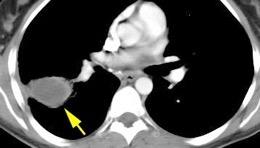

Shock hipovolémico tras puñalada.

Hemotórax

Coágulo centinela

Pedrosa I et al. Intercostal artery injury manifested by a sentinel pleural clot. Emerg Radiol 2001